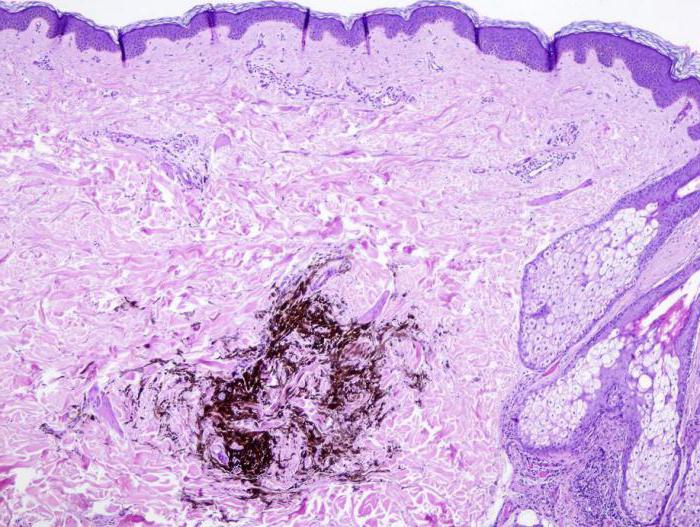

Как отличить от других новообразований невус? Родинка обладает сине-черной, темно-синей или же голубой окраской. Объяснить такой специфический оттенок можно большим скоплением в слоях кожных покровов большого количества меланина. Создается впечатление, что это не невус, а инородное тело.

Если существует вероятность образования меланомы, голубой невус удаляется вместе с участком здоровой кожи, после чего отправляется на гистологический анализ для определения природы его возникновения.

В некоторых случаях требуется определить скопление меланоцитов в слоях кожных покровов. Для этого проводится гистологическое исследование.

Постепенный рост голубого невуса встречается редко и вызывает подозрение на меланому. Хотя, перерождение в меланому, на самом деле, редко. Голубой невус, обычно, имеет типичные клинические появления. Равномерная окраска и симметричный вид, стабильность образования, помогут отличить его от меланомы. Тем не менее, внезапное появление голубого невуса может затруднить диагностику от узловой меланомы. Чаще всего встречается перерождение в меланому сотового (целюлярного) голубого невуса. Волосистая часть головы — наиболее распространенная область. Рост прежде стабильного невуса, появления кровоточивости, изменение окраски, дискомфорт, должны вызвать подозрение. Рост может привести к постепенному увеличению опухоли до нескольких сантиметров в диаметре и бугристости. Лимфоузлы чсто поражаются метастазами, либо рядом образуются подобные более мелкие очаги меланомы. Голубые невусы встречаются во влагалище, на шейке матки, в лимфоузлах. Соответственно, меланома может образоваться и там. Эксцизионная биопсия с полным удалением невуса и исследование под микроскопом показаны в случаях, когда диагноз меланомы не может быть исключён. Меланома из голубого невуса лечится так же, как и любая другая, в основном, хирургическим методом.